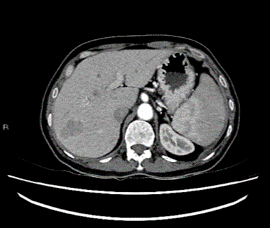

Figure 2A: Arterial phase computed tomography scan of the liver. Lesion in segment VII remained hypodense when compared to surrounding liver parenchyma.

We proceeded with a computed tomography of the liver (CT liver) for further evaluation. CT liver showed a 4.3 x 2.4cm heterogeneously hypodense lobulated mass in segment VII of the liver. The mass was hypodense to the liver on all phases (plain, arterial, venous and delayed). There was mild heterogeneous enhancement, but there was no arterial enhancement (Figure 2A), washout (Figures 2B & 2C) or pseudo capsule, which should be expected in hepatocellular carcinoma. In view of the known history of thalassemia and the presence of paravertebral soft tissue masses that were likely to be extramedullary haematopoiesis, the possibility of extramedullary haematopoiesis was suggested. The other lesion was a 0.9cm hypodensity in segment VI of the liver, which was diagnosed as a flash-filling haemangioma. A magnetic resonance imaging (MRI) was then ordered for the indeterminate segment VII lesion. On MRI, the hepatic segment VII mass in question showed mild heterogeneous contrast enhancement but no appreciable arterial enhancement, washout or pseudo capsule (Figure 3A & Figure 3B).